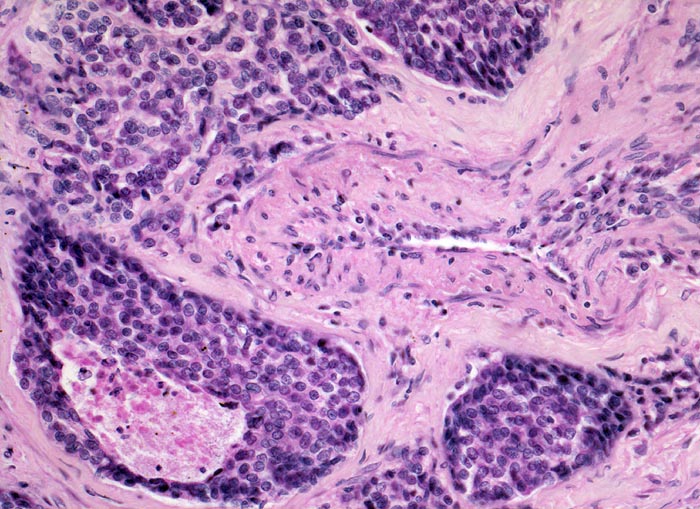

• Das Karzinom ist aufgebaut aus tubulären und kribriformen Drüsen.

• In den sternförmigen Ausläufern finden sich erweiterte Endothelausgekleidete Lymphgefässe in der Nachbarschaft von Blutgefässen.

• Die erweiterten Lymphgefässe enthalten solide Tumorzellaggregate.